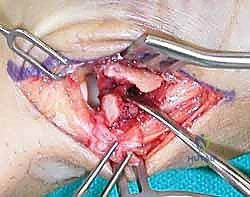

2. الرد المفتوح والتثبيت الداخلي (ORIF - Open Reduction and Internal Fixation)

عندما يكون الكسر مفتتًا (مثل كسر رولاندو) أو لا يمكن رده بشكل مغلق، يتم اللجوء إلى الجراحة المفتوحة.

* الخطوات: يقوم الجراح بعمل شق جراحي دقيق (غالباً بشق Wagner) فوق قاعدة الإبهام للوصول المباشر إلى المفصل.

* يتم تجميع الشظايا العظمية بدقة متناهية تحت التكبير الجراحي (Microsurgery).

* يتم تثبيت العظام باستخدام شرائح تيتانيوم صغيرة جداً (Mini-plates) ومسامير دقيقة (Screws).

* الميزة: يوفر تثبيتاً صلباً جداً (Rigid Fixation) يسمح ببدء العلاج الطبيعي وحركة المفصل في وقت مبكر جداً، مما يقلل من التيبس.